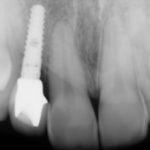

Charles P.

This patient had an Implant placed to replace a missing molar which had been removed due to infection.